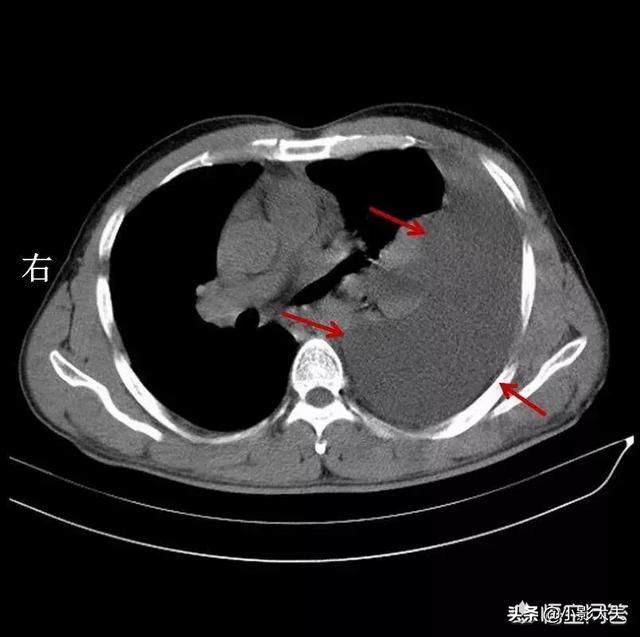

肺疾患や胸部疾患は、胸部圧迫感、喉頭、気管、太い気管支の炎症、腫瘍や異物、気胸、胸水、喘息、慢性閉塞性肺疾患、肺水腫、びまん性肺線維症、広範な実質病変、腫瘍、サルコイドーシス、肺無気肺、肺塞栓症などの原因となります。では、胸部X線検査や胸部CT検査を受け、呼吸器内科を受診する理由はあるのでしょうか?

これには、気管支炎、肺炎、びまん性間質性肺疾患、胸水貯留、自然気胸、広範な胸膜癒着などの肺の最も一般的な呼吸器系疾患、重度の貧血、メトヘモグロビン血症などの血液系疾患、亜硝酸塩中毒や一酸化炭素中毒、不安や抑うつなどの精神医学的要因が含まれ、これらすべてが胸部圧迫感を引き起こす可能性がある。

2.呼吸器系の疾患

呼吸器系も胸部にあり、呼吸器系に病気があると胸が締め付けられるような症状が現れる。例えば、肺がんでは気管支が閉塞し、胸が締め付けられるような息切れが起こります。例えば、高齢者の慢性肺気腫による心臓病でも胸のつかえが現れます。多量の胸水が肺を圧迫する場合にも胸が締め付けられることがあります。